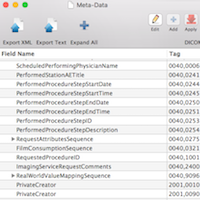

DICOM Standard 2016

DICOM Standard 2016